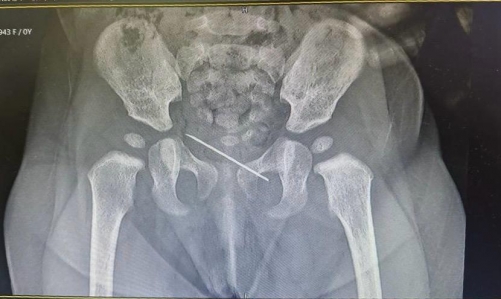

Upon examination, the medical team, led by Dr. Shivananda and assisted by Dr. Muhammed Salim P.U., discovered a broken syringe needle measuring approximately 3.5 centimetres lodged in the subcutaneous layer on the mons pubis.

The needle was promptly removed under local anaesthesia, ensuring the infant’s safety. Following the successful surgical intervention, the infant was discharged from the hospital, bringing immense joy and pride to the entire Al Hilal team and the infant’s parents.